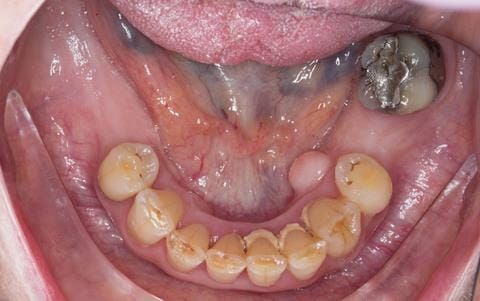

- Eight mandibular anterior teeth worn incisal edges from now extracted maxillary anterior crowns. Gingivitis - owing to inadequate oral hygiene.

- LL6 with large amalgam restoration - healthy periodontium.

- Bruxism.